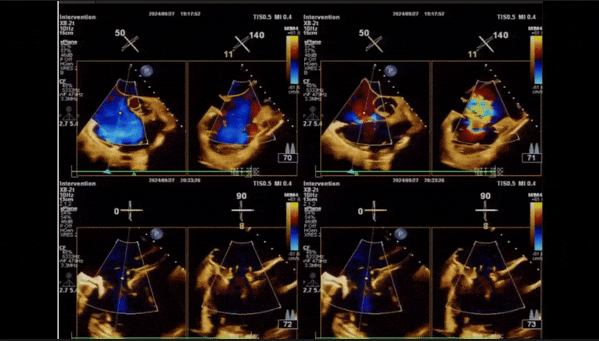

術(shù)后即刻返流

術(shù)后即刻經(jīng)食道超聲可見(jiàn),三尖瓣假體瓣膜位置合適,牛心包瓣葉運(yùn)動(dòng)狀態(tài)良好,開(kāi)閉正常,瓣周及瓣葉對(duì)合緣處未見(jiàn)明顯返流,心電圖及心包狀態(tài)較術(shù)前無(wú)明顯變化。

術(shù)前術(shù)后返流情況對(duì)比